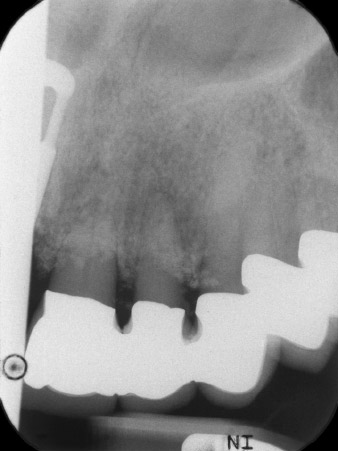

Рентгеновата снимка показа хоризонтална загуба на кост около зъби 21 и 22 (Фиг. 1). Когато короната е отстранена, тези зъби са били неумишлено екстрахирани с нея.